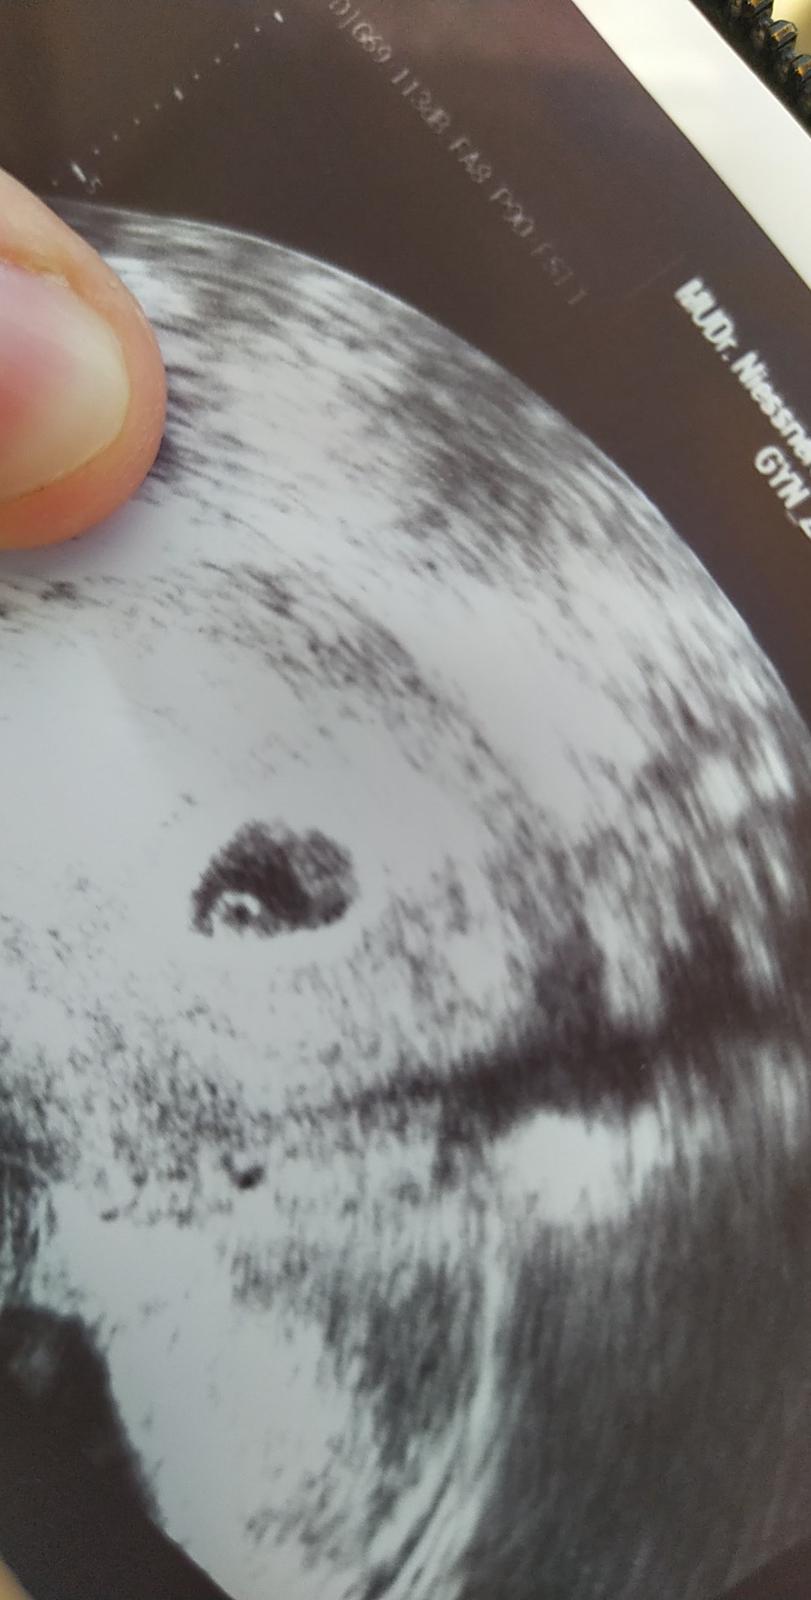

No a dnes jsem byla na gynekologii a dr viděla pouze gestacni a zloutkovy vacek je to ok v tomhle týdnů.. Byl tam zástup a nebyl moc milý...

@kiki01109 já měla úplně ten stejný obraz na UZ v 5+4🙂 na kontrole 6+6 uz byl vidět maličký plod a srdeční akce. Pokud ovulace byla skutečně jak píšeš, je to úplně v pořádku🙂